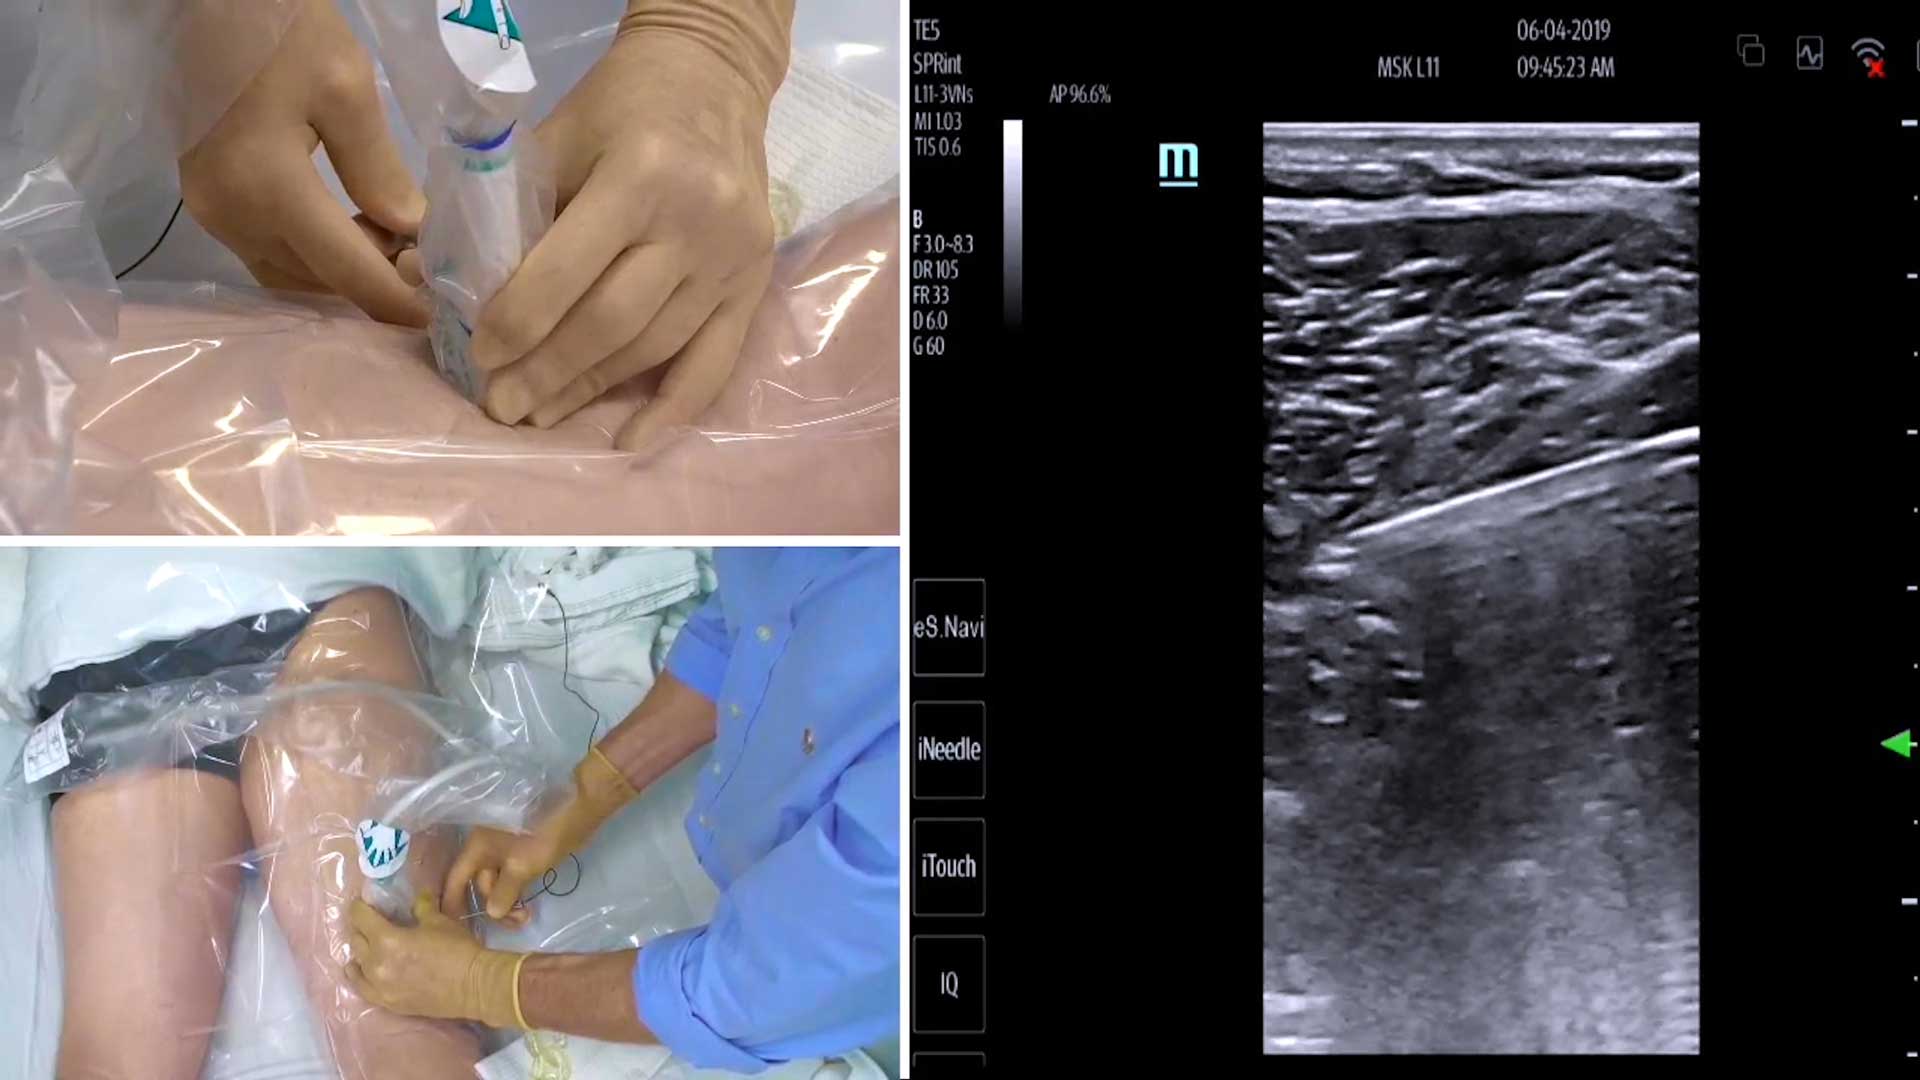

Video: Ultrasound-Guided Peripheral Nerve Stimulation for Postoperative Pain Management

Video: Ultrasound-Guided Peripheral Nerve Stimulation for Postoperative Pain Management Brian Ilfeld, MD, MS, talked with the Pain Management Collaboratory Coordinating Center about his pragmatic clinical trial (PCT) with the PMC.  Dr. Ilfeld is the principal investigator of Ultrasound Guided Percutaneous Peripheral Nerve Stimulation: A Nonpharmacological Alternative for the Treatment of Postoperative Pain, one of the